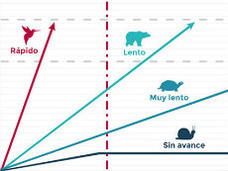

Progreso contra el cáncer: El papel de la ciencia básica

Progreso contra el cáncer: El papel de la ciencia básica

Tendencias del cáncer: Influjo en la atención y en prioridades de investigación

Muchas de las tendencias que observamos en el cáncer están cambiando cómo vemos el cáncer y cómo respondemos a él, desde impulsar la investigación hasta identificar las causas fundamentales de los cánceres que están aumentando en incidencia para dar forma a la investigación sobre el tratamiento y la prevención del cáncer.